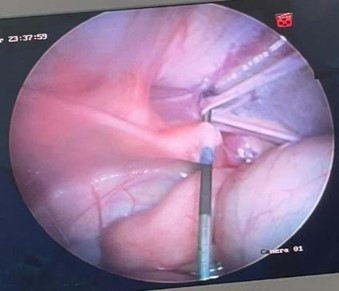

El abordaje inicial laparoscópico se realiza mediante acceso umbilical abierto e introducción de trocar umbilical de 10 mm, con neumoperitoneo 12 mmHg, 5 L/min. Luego introducimos cámara y realizamos laparoscopia de cavidad, observamos el anillo inguinal interno izquierdo cerrado y anillo inguinal interno derecho permeable. Posteriormente, se introdujo hilo prolene 2.0 en la aguja epidural en forma de una lazada (primer hilo) en región inguinal derecha de manera percutánea (véase figura 3), se bordeó el anillo atravesando el peritoneo (figura 4). Se retiró la aguja dejando el hilo en forma de lazada en cavidad, después se introdujo, del mismo modo, material prolene 2.0 (segundo hilo) en forma simple, para localizar la lazada e introducir ese hilo en la lazada (figura 5). Se retiró aguja y, a través de la lazada, al extraer el hilo en forma de lazada, se rescató el segundo hilo que efectuó el cierre del anillo inguinal interno (figura 6), realizándose cierre del defecto por técnica de PIRS. Por último, el defecto aponeurótico en región umbilical se suturó con Vicryl 2-0.

Figura 5. Retiro de aguja e introducción de material prolene 2.0

Nota: se retira la aguja dejando el hilo en cavidad, se introduce de igual forma material prolene 2.0 (2do hilo) en forma simple para localizar la lazada e introducir ese hilo en la lazada.

Figura 6. Retiro de aguja y cierre de anillo inguinal interno

Nota: se retira aguja, y a través de la lazada al extraer el hilo en forma de lazada, se rescata el segundo hilo que va a hacer el cierre del anillo inguinal interno.